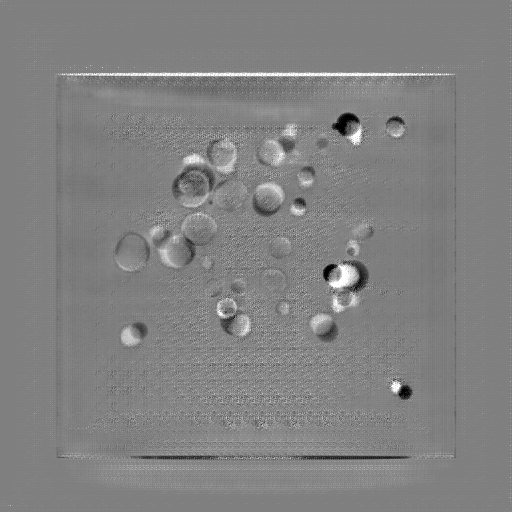

Refer to caption

(a) Orthogonal 0superscript00^{\circ}

(b) Perspective 0superscript00^{\circ}

(c) Perspective deformation ((b)-(a))

(d) Perspective 180superscript180180^{\circ}

(e) Difference of Perspective 0superscript00^{\circ} and 180superscript180180^{\circ}

(f) RGB 0superscript00^{\circ} and 180superscript180180^{\circ}

Figure 6: An example for perspective deformation learning from dual complementary views: (a) the orthogonal projection of the 3D bead phantom from the 0superscript00^{\circ} view; (b) the perspective projection from the 0superscript00^{\circ} view; (c) the difference image between (b) and (a); (d) the perspective projection from the 180superscript180180^{\circ} view; (e) the difference image between (d) and (b); (f) the RGB stack of the 0superscript00^{\circ} and 180superscript180180^{\circ} perspective projection images, where the magenta and green areas correspond to the positive (bright) and negative (dark) areas in (e). The intensity range [0, 11] is converted to [0, 255] for visualization.

Note that when and only when z=0𝑧0z=0, which is m=m=1superscript𝑚𝑚1m^{\prime}=m=1, d180subscript𝑑superscript180d_{180^{\circ}} and dPDsubscript𝑑PDd_{\text{PD}} both equal to 0. This provides a practical way to observe which structures suffer from perspective deformation by assessing deviations between the two complementary views.

The orthogonal and perspective projection images of the same 3D bead phantom in a complementary view setting are displayed in Fig. 6. Fig. 6(c) shows the perspective deformation, which is the difference between the perspective projection (Fig. 6(b)) and the orthogonal projection (Fig. 6(a)) from the 0superscript00^{\circ} view. Fig. 6(c) clearly demonstrates that the magnitude of perspective deformation increases from the center outwards radially. The 180superscript180180^{\circ} perspective projection image is displayed in Fig. 6(d) and its difference with respect to the 0superscript00^{\circ} perspective projection is displayed in Fig. 6(e). Fig. 6(e) is similar to Fig. 6(c) in bead areas, which illustrates that the deviation between two complementary views has strong correlation to perspective deformation. To integrate such dual-view information, like Fig. 5(d), we convert the perspective projections images from the 0superscript00^{\circ} and 180superscript180180^{\circ} views to a 3-channel RGB image in Fig. 6(f). The red and blue channels use images from the 0superscript00^{\circ} view, while the green channel uses images from the 180superscript180180^{\circ} view. In the RGB images, the color reveals the intensity difference between the 0superscript00^{\circ} and 180superscript180180^{\circ} perspective projection images. Grey areas contain close intensity values from both views. Instead, magenta and green areas indicate larger intensity values from the 0superscript00^{\circ} and 180superscript180180^{\circ} views respectively, where perspective deformation correction is necessary. They correspond to the positive (bright) and negative (dark) areas in the difference image in Fig. 6(e). In Fig. 6(f), the magenta beads and their corresponding green beads are located close to each other, which allows a network with limited receptive field size to capture bead-to-bead (point-to-point) dependency.